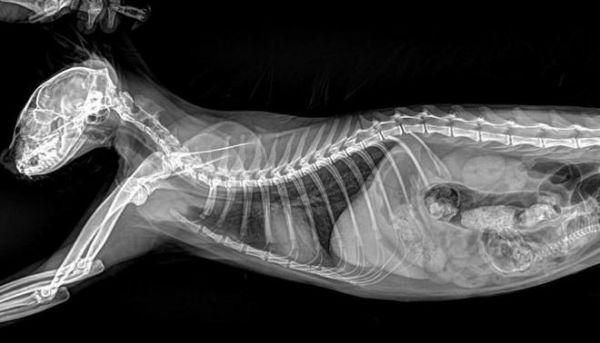

必康宠物DR以实测数据彰显高清硬实力:经线对卡实测,成像分辨率均值可达3.7lp/mm,峰值可达4.0lp/mm,远超行业常规标准,细微到0.1mm的骨骼裂纹、脏器微小结节,甚至是纤细如发丝的血管、豌豆大小的淋巴结,都能清晰可辨。临床应用中,无论是小型犬的隐匿性骨折、猫咪的早期骨裂,还是兔子上臼齿牙根异常生长压迫眼球的复杂病例,必康DR都能精准捕捉病灶细节,清晰呈现病变位置、大小与形态,帮助兽医快速锁定病因,为后续治疗筑牢诊断根基。

某宠物医院接诊一只精神萎靡、眼球突出的兔子,疑似严重牙科疾病,常规DR拍摄的影像模糊,无法清晰呈现齿根状态,难以确诊。借助必康宠物DR的高清成像与AI器官分割功能,设备快速捕捉影像,清晰呈现兔子右臼齿的过长、歪斜,以及齿根穿透牙槽骨、压迫眼球后方的细节,AI伪彩增强进一步凸显病变区域,兽医几分钟内便精准确诊,为后续手术治疗争取了宝贵时间,也让宠主看到了希望。